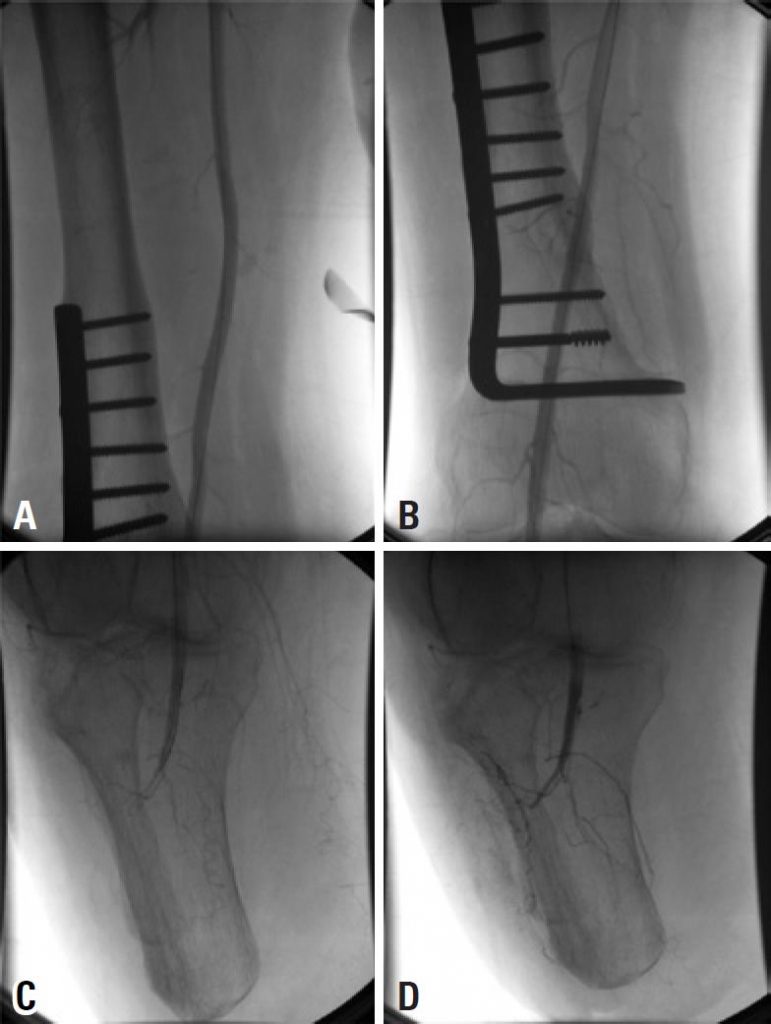

Preservation of the knee joint has enormous advantages in terms of mobility and rehabilitation of an amputee. Any cause of breakdown requiring revision to an above-knee amputation is a major setback because it reduces the patient’s rehabilitative potential. We report a case of intra-arterial thrombolysis use to save a below-knee amputation stump with acute ischemia. A 56-year-old man who sought the emergency department with 1-day history of acute pain on his right below-knee stump. The angiography confirmed popliteal artery occlusion. Pharmacomechanical thrombectomy, with Aspirex (rotational catheter to restore blood flow in occluded vessel, by removing occlusion material from the vessel) and recombinant tissue plasminogen activator, was performed. After 9 years of follow-up the patient remained asymptomatic, capable of independent ambulation with prosthetic limb. Intra-arterial fibrinolysis seems to be a safe and effective treatment for cases of acutely ischemic amputation stump.